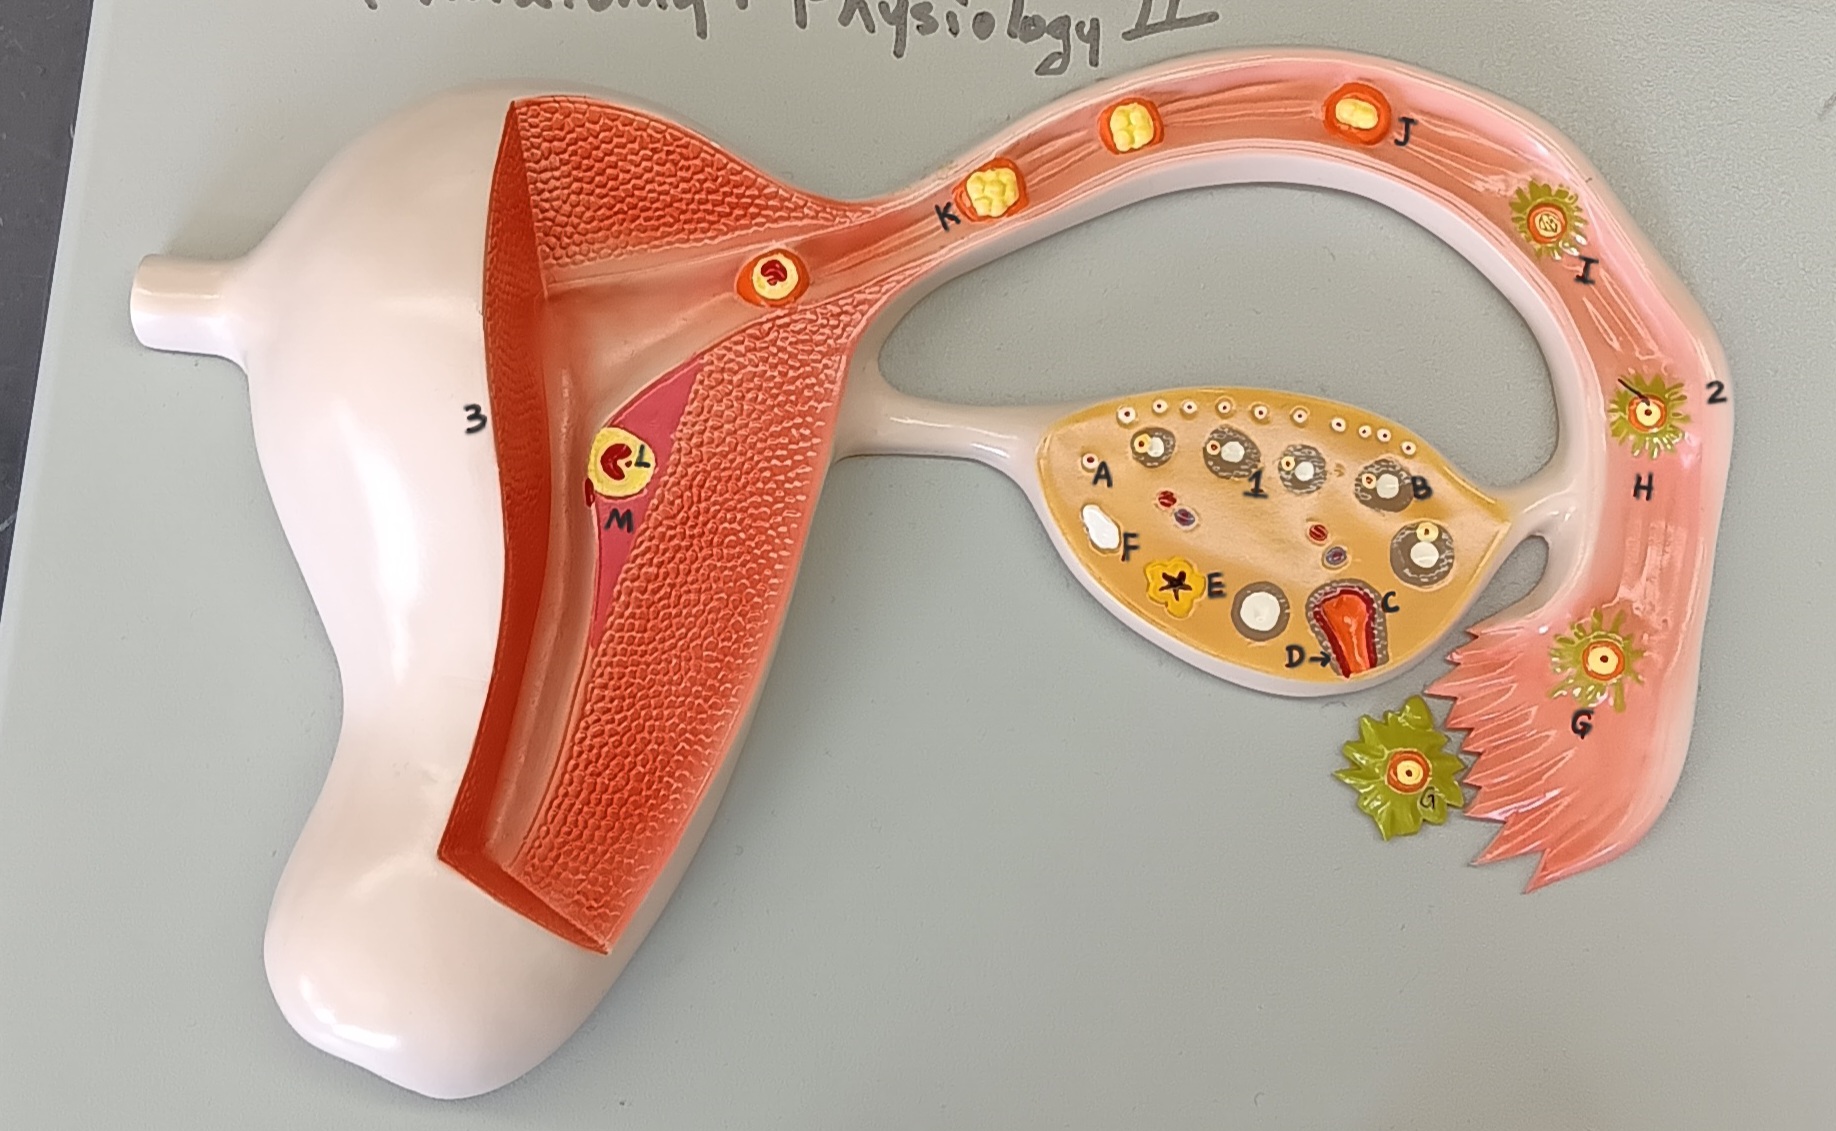

ovary

1

primordial follicle

a

secondary follicle

b

ruptured follicle

c

granulosa cells

d

corpus luteum

e

secondary oocyte

g

ovum

h

zygote

i

blastocyst

l

endometrium

m

corpus albicans

f

uterus

3

fallopian tube

2